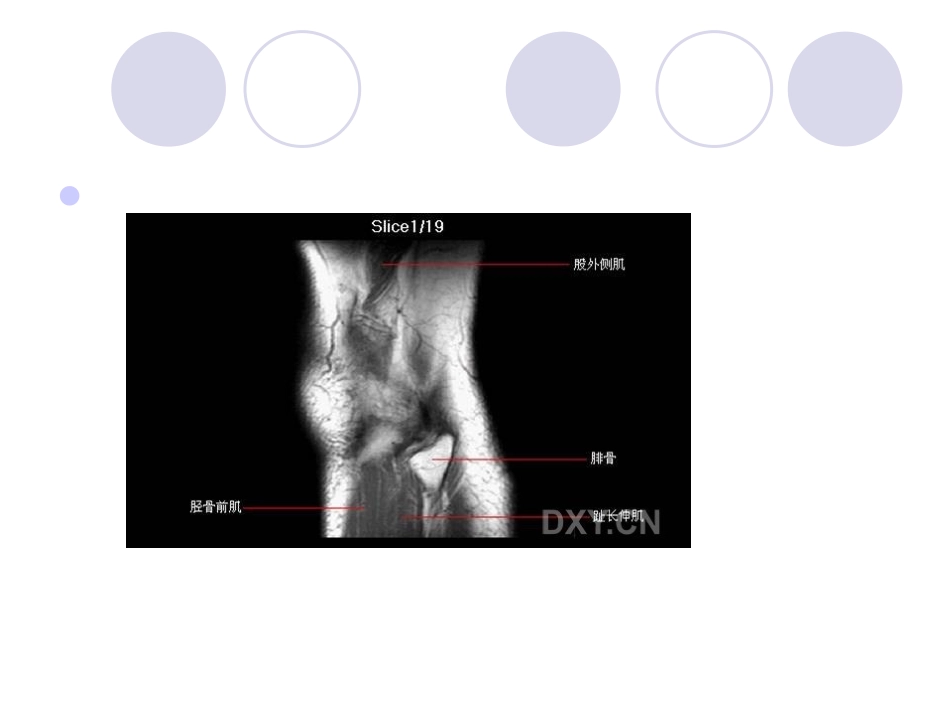

膝关节MRI膝关节MRI诊断之半月板病变半月板损伤是膝关节疼痛的常见原因之一,传统的X线平片及CT扫描不能显示半月板,X线关节造影及CT关节造影虽能显示半月板,但因属于微创伤检查,且CT扫描角度的限制,所以临床上很少应用。磁共振成像因具有高的组织分辨率,可以多方位、任意面成像,是目前检查半月板最好和首选的检查方法。正常半月板在MRI的各个序列中均表现为均匀的低信号影,半月板损伤表现为半月板形态、边缘、大小及其内部信号的改变,按Mink和Fischer提出的方法进行分级1半月板Ⅰ级损伤即早期退变(或变性),在病理上表现为灶性的或早期的半月板粘液样变性,这是由于半月板内纤维软骨基质内的粘多糖产物的增加所致。在MRI的T2WI上表现为半月板内点片状或类圆形高信号影,未达到...